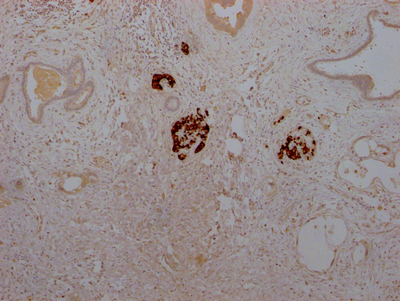

IHC image of CSB-RA584163A0HU diluted at 1:100 and staining in paraffin-embedded human pancreatic cancer performed on a Leica BondTM system. After dewaxing and hydration, antigen retrieval was mediated by high pressure in a citrate buffer (pH 6.0). Section was blocked with 10% normal goat serum 30min at RT. Then primary antibody (1% BSA) was incubated at 4℃ overnight. The primary is detected by a Goat anti-rabbit IgG polymer labeled by HRP and visualized using 0.05% DAB.